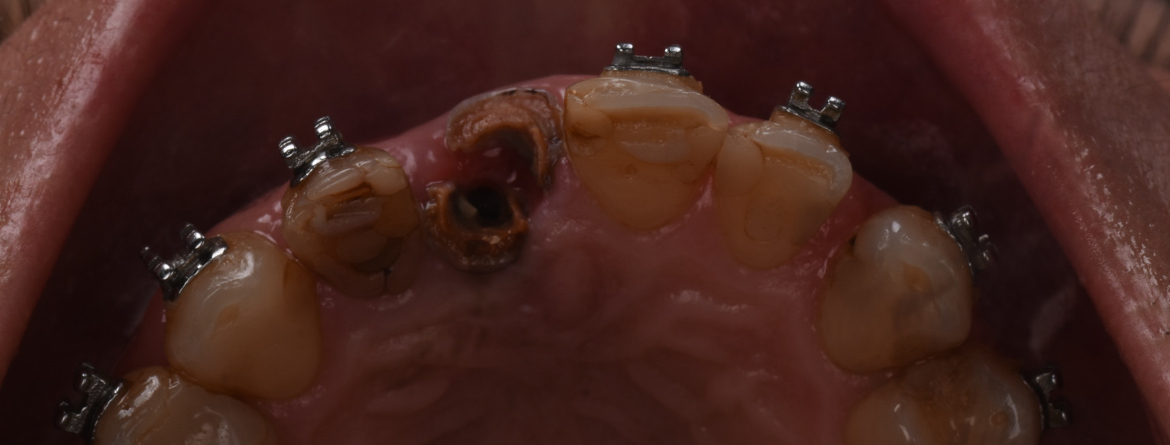

Uma das decisões de planeamento e tratamento mais desafiadoras em dentisteria restauradora é a manutenção de um dente obturado ou a sua extração e substituição por um implante. Tomar uma decisão informada depende não apenas da experiência clínica e perícia, mas também da interpretação das evidências clínicas publicadas. Nos últimos anos, dados mais robustos e um exame clínico mais detalhado ajudam a compreender as vantagens e desvantagens de cada uma das possibilidades de tratamento.

Este curso tem como objetivo auxiliar nas opções de planeamento entre o tratamento endodôntico e a substituição por um implante dentário, que apesar de terem características muito diferentes partilham o objetivo comum de servirem de pilar a uma reabilitação.